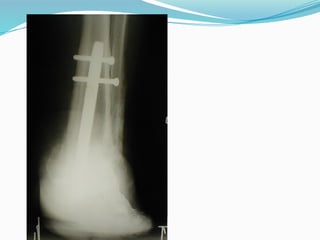

X-ray Imaging

Plain X-rays

- Osteomyelitis,

fractures

- Soft tissue gas

- Dislocations in

neuropathic arthropathy